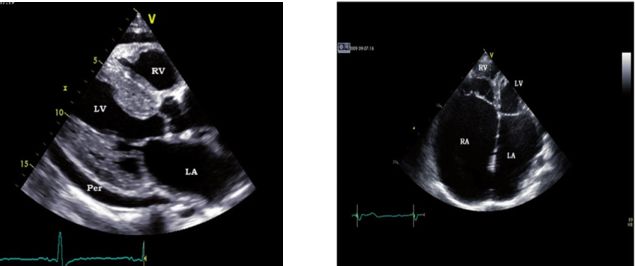

A图:二维超声左室长轴显示左室壁肥厚和心包积液 RA,右心房;RV,右心室;LV,左心室;LA,左心房;AO,主动脉;

B图:心尖四腔示左房及右房明显扩大,左房容积120ml,LA容积指数 =120ml/1.75m2=68.57 mL/m2